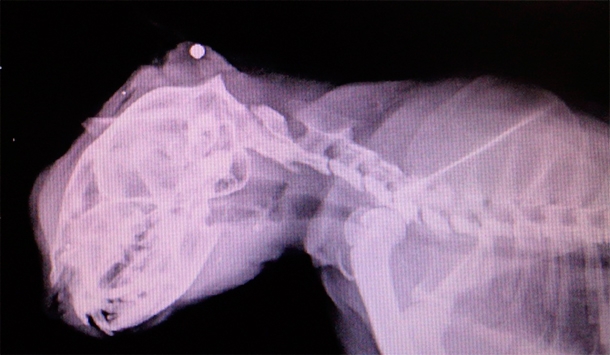

Несчастное и искалеченное животное обнаружили на улице случайные прохожие. Они незамедлительно принесли его в ветеринарную клинику. Врач после осмотра кота отправил его на рентген. Когда снимок был готов, выяснилось, что животному чудом удалось выжить, сообщается на странице ветеринарной клиники "Панацея" в социальной сети "ВКонтакте".

В затылочной части черепа застряла пуля из автоматической винтовки. Ветеринары тут же приняли решение во что бы то ни было спасти кота. Как позже рассказала врач, проводившая операцию, пулю сразу же извлекли, однако животному пришлось перенести не одно хирургическое вмешательство, а целых два. Ему также собрали два перелома нижней и верхней челюстей. Коту-герою дали кличку Киря. Пока он до сих пор живет в клинике, однако волонтеры очень надеются, что в скором времени животное реабилитируется и найдет себе новых хозяев.